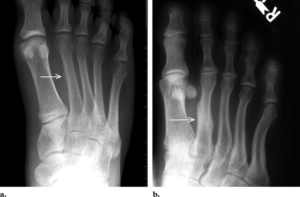

Перелом Джонса

Одной из разновидностей подобных травм является перелом Джонса. Это перелом 5 плюсневой кости со смещением, при котором медленно срастаются отломки. После него у некоторых пациентов кость не срастается никогда.

Зачастую пациентам могут произвести неправильное диагностирование. В результате назначают лечение растяжения связок стопы.

Наибольшую опасность представляет собой перелом основания. Он часто сопряжен с вывихом или нестабильностью сустава Лисфранка и разрывом связочного аппарата.

Также усиленное внимание травматологи уделяют лечению переломов в области метафизарно-диафизарного перехода. Травма также сопряжена с повреждением предплюсне-плюсневого сустава и растяжением связочного аппарата.